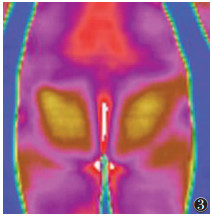

2 结果 2.1 治疗前患者局部代谢热形态根据采集的图像显示,寒湿凝滞型患者的子宫区周边、宫颈区可见明显的细胞代谢热降低区(图 1);代谢热值及热辐射值相对较低,边界清晰,形态较规则,检查过程中可见代谢热从周边向子宫及宫颈区走行(图 2);与两侧腹股沟淋巴联系不密切,且腹股沟淋巴对称,未见明显代谢热差值,下腹部及腰骶部未见异常热源(图 3)。

| 图 2 女,24岁,原发性寒湿凝滞型痛经,代谢热从周边向子宫及宫颈区走行 |